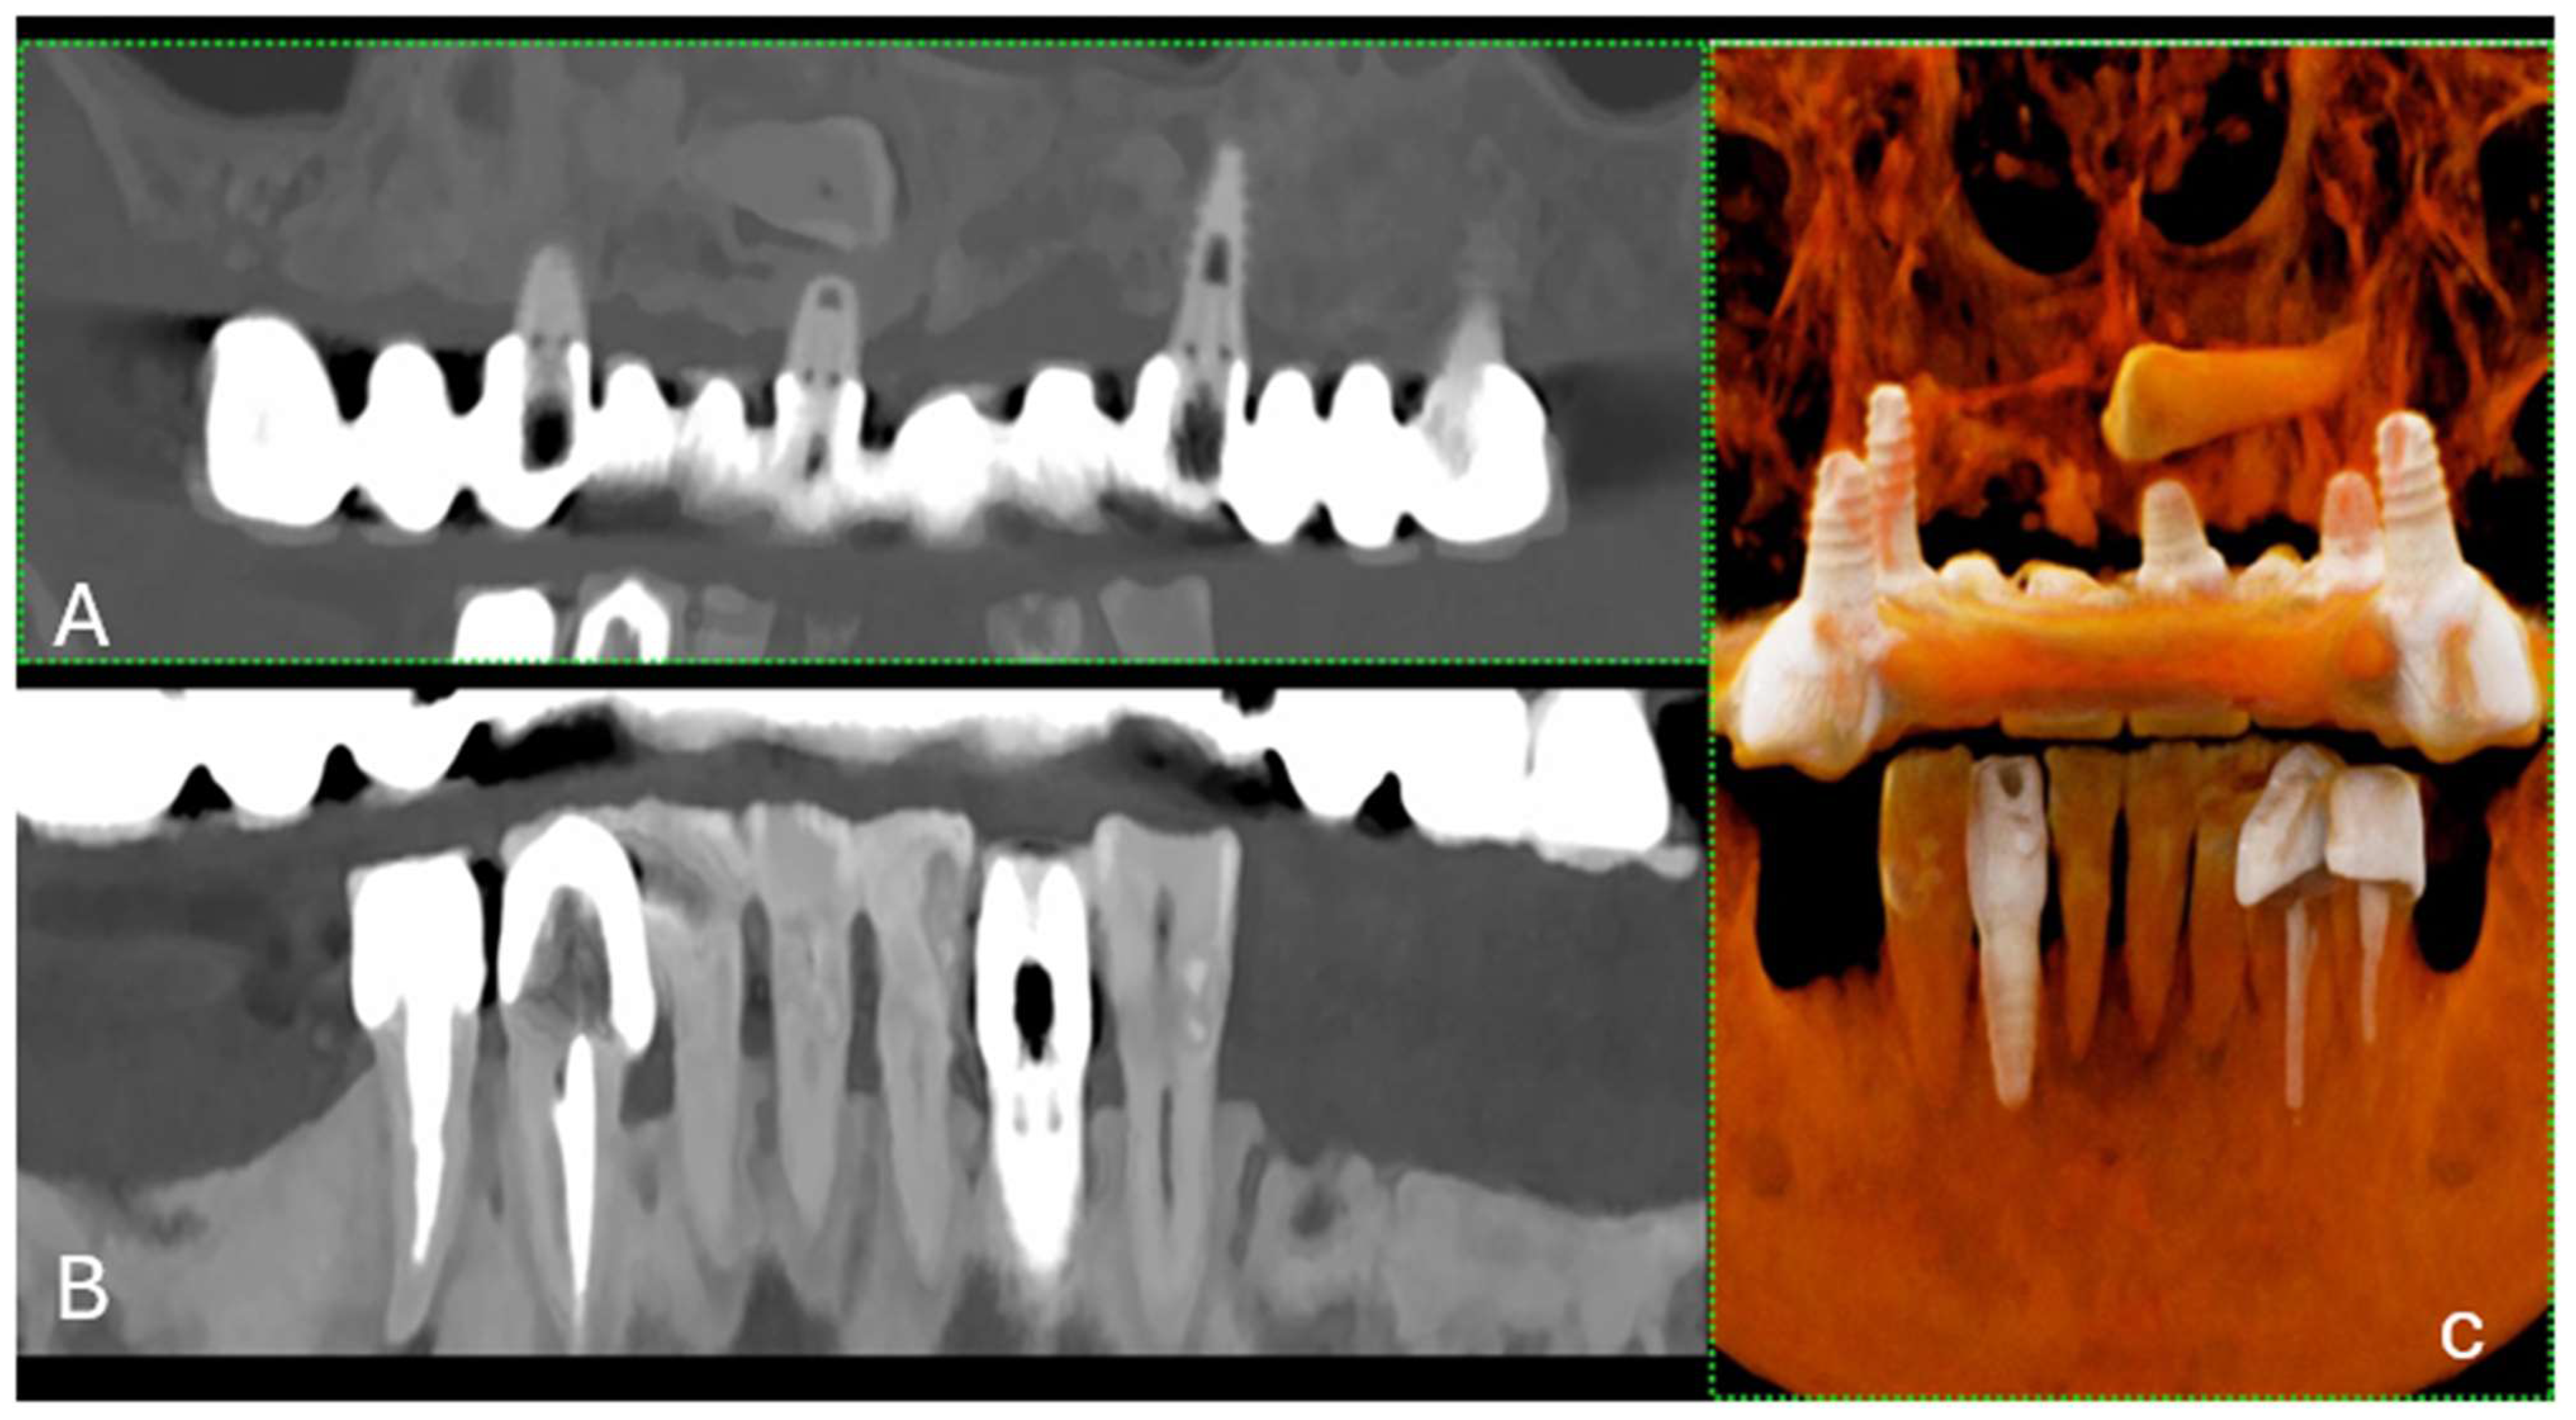

Figure 2. (A) The curved MPR of the upper and lower jaws, the roots of the teeth, and the surrounding bone structure, which is commonly used to assess overall dental health, including bone levels and root configurations, and to check for any abnormalities such as impacted teeth or pathologies in the jawbone. (B) Front-view 3D cinematic rendering of the jaws and teeth, which shows the relative positions of the teeth in both the upper and lower jaws. This type of visualization helps to assess the bite, spacing, and alignment of the teeth, as well as the relationship between the upper and lower dental arches. The scan was performed on a commercial whole-body Dual Source Photon Counting CT scanner (NAEOTOM Alpha, Siemens Healthineers); 0.2 mm slice thickness, 0.1 mm reconstruction increment, FOV 140 mm, spiral acquisition with tube current modulation; resolution matrix of 1024 × 1024 pixels on the source axial reconstructions with a kernel filtering of Bv72; maximum intensity of Quantum Iterative Reconstruction (QIR 4). The actual displayed resolution is 0.1 mm (100 microns). Abbreviations: 3D, three-dimensional; MPR, multiplanar reconstruction; FOV, field-of-view.

The evolution of CT technology has paralleled advancements in computer science, X-ray production, and detection, culminating in novel applications, such as dual-energy CT (DECT) for medical imaging [1]. A significant leap has been made with the introduction of energy-resolving photon-counting detectors (PCDs), which are distinguished by their ability to discern the energy of individual X-ray photons, offering improved spatial resolution, noise reduction, dose efficiency, and spectral imaging [1]. The introduction of clinical photon-counting CT (PCCT) systems in 2021 has led to significant advancements in CT technology, offering the potential for lower patient doses and higher spatial resolution owing to smaller detector pixels [2,3,4,5,6]. This innovation is poised to update clinical applications, particularly in anatomical imaging, by providing clearer images of dental structures (5). PCCT promises to provide high-resolution images (up to 100 µm), superior soft-tissue contrast, and faster scanning times, which are crucial for detailed dental diagnoses and treatment planning (Figure 1 and Figure 2).